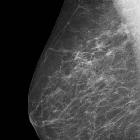

In breast imaging, forbidden, check or review areas are zones that, according to Tabár, require special attention in mammographic interpretation. These are:

- on a mediolateral oblique (MLO) view

- the "Milky Way" (retromammary fat): a 3-4 cm wide band parallel to the edge of the pectoral muscle

- retroareolar space

- on a craniocaudal (CC) view

- the medial half of the breast

- "no man's land": retroglandular clear space between the posterior border of the breast parenchyma and the chest wall on any view, especially on the CC view

The definition "forbidden areas" is based on the incidence and distribution of cancer or de novo cancers identified in screening, demonstrating clusters located in the tail and in the inframammary fold on the MLO view, and in the tail, centrally and in the medial portions of the breast on the CC view. This warrants neutral radiographic position (no medial or lateral rotation).